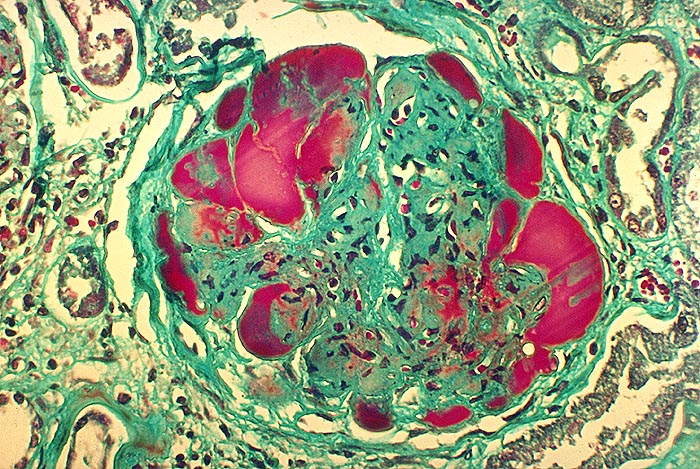

Diabetische noduläre Glomerulosklerose: Exsudative Läsion

Die peripheren Glomerulusschlingen werden durch riesige Proteinthromben vollständig ausgefüllt (exsudative Läsion). Das Mesangium ist massiv verbreitert infolge Matrixvermehrung. Auch im Mesangium sind einzelne Proteinablagerungen erkennbar. Auffallend in diesem Glomerulus ist auch der Zellreichtum des Mesangiums.

Diese exsudativen Läsionen wurden früher als fibrinoide Schlingenkappen bezeichnet. Es handelt sich aber nicht um Proteinablagerungen auf der Aussenseite der Glomerulusschlingen, sondern vielmehr um Proteinthromben, die aneurysmatische Glomerulsusschlingen vollständig aufsüllen.